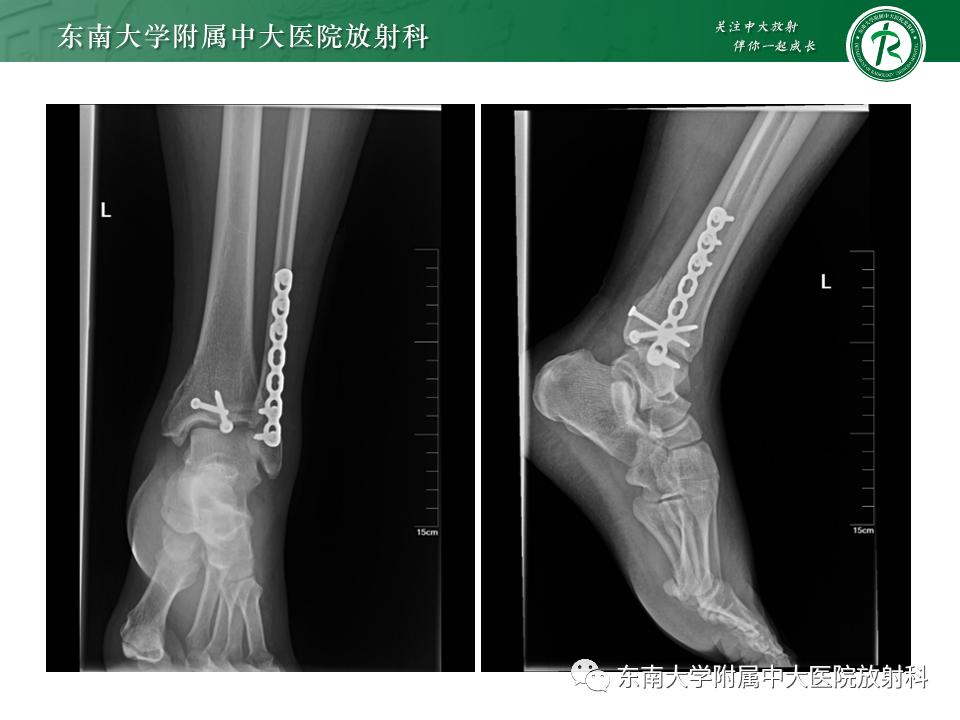

影像学表现

左腓骨下段骨折伴下胫腓联合分离,好文分享深度揭秘